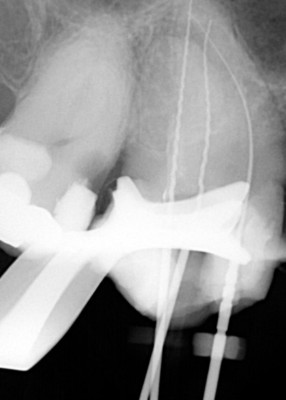

Udrożnienie kanału, w którym zostało złamane narzędzie pozwala wypełnić poprawnie kanały zęba i zachować go z dobrym rokowaniem na kolejne lata.

Usuwanie złamanych narzędzi w powiększeniu oraz opracowywanie trudnych anatomicznie kanałów zębów, które odbywa się pod mikroskopem i jest gwarancją, że leczenie będzie przeprowadzone poprawnie.